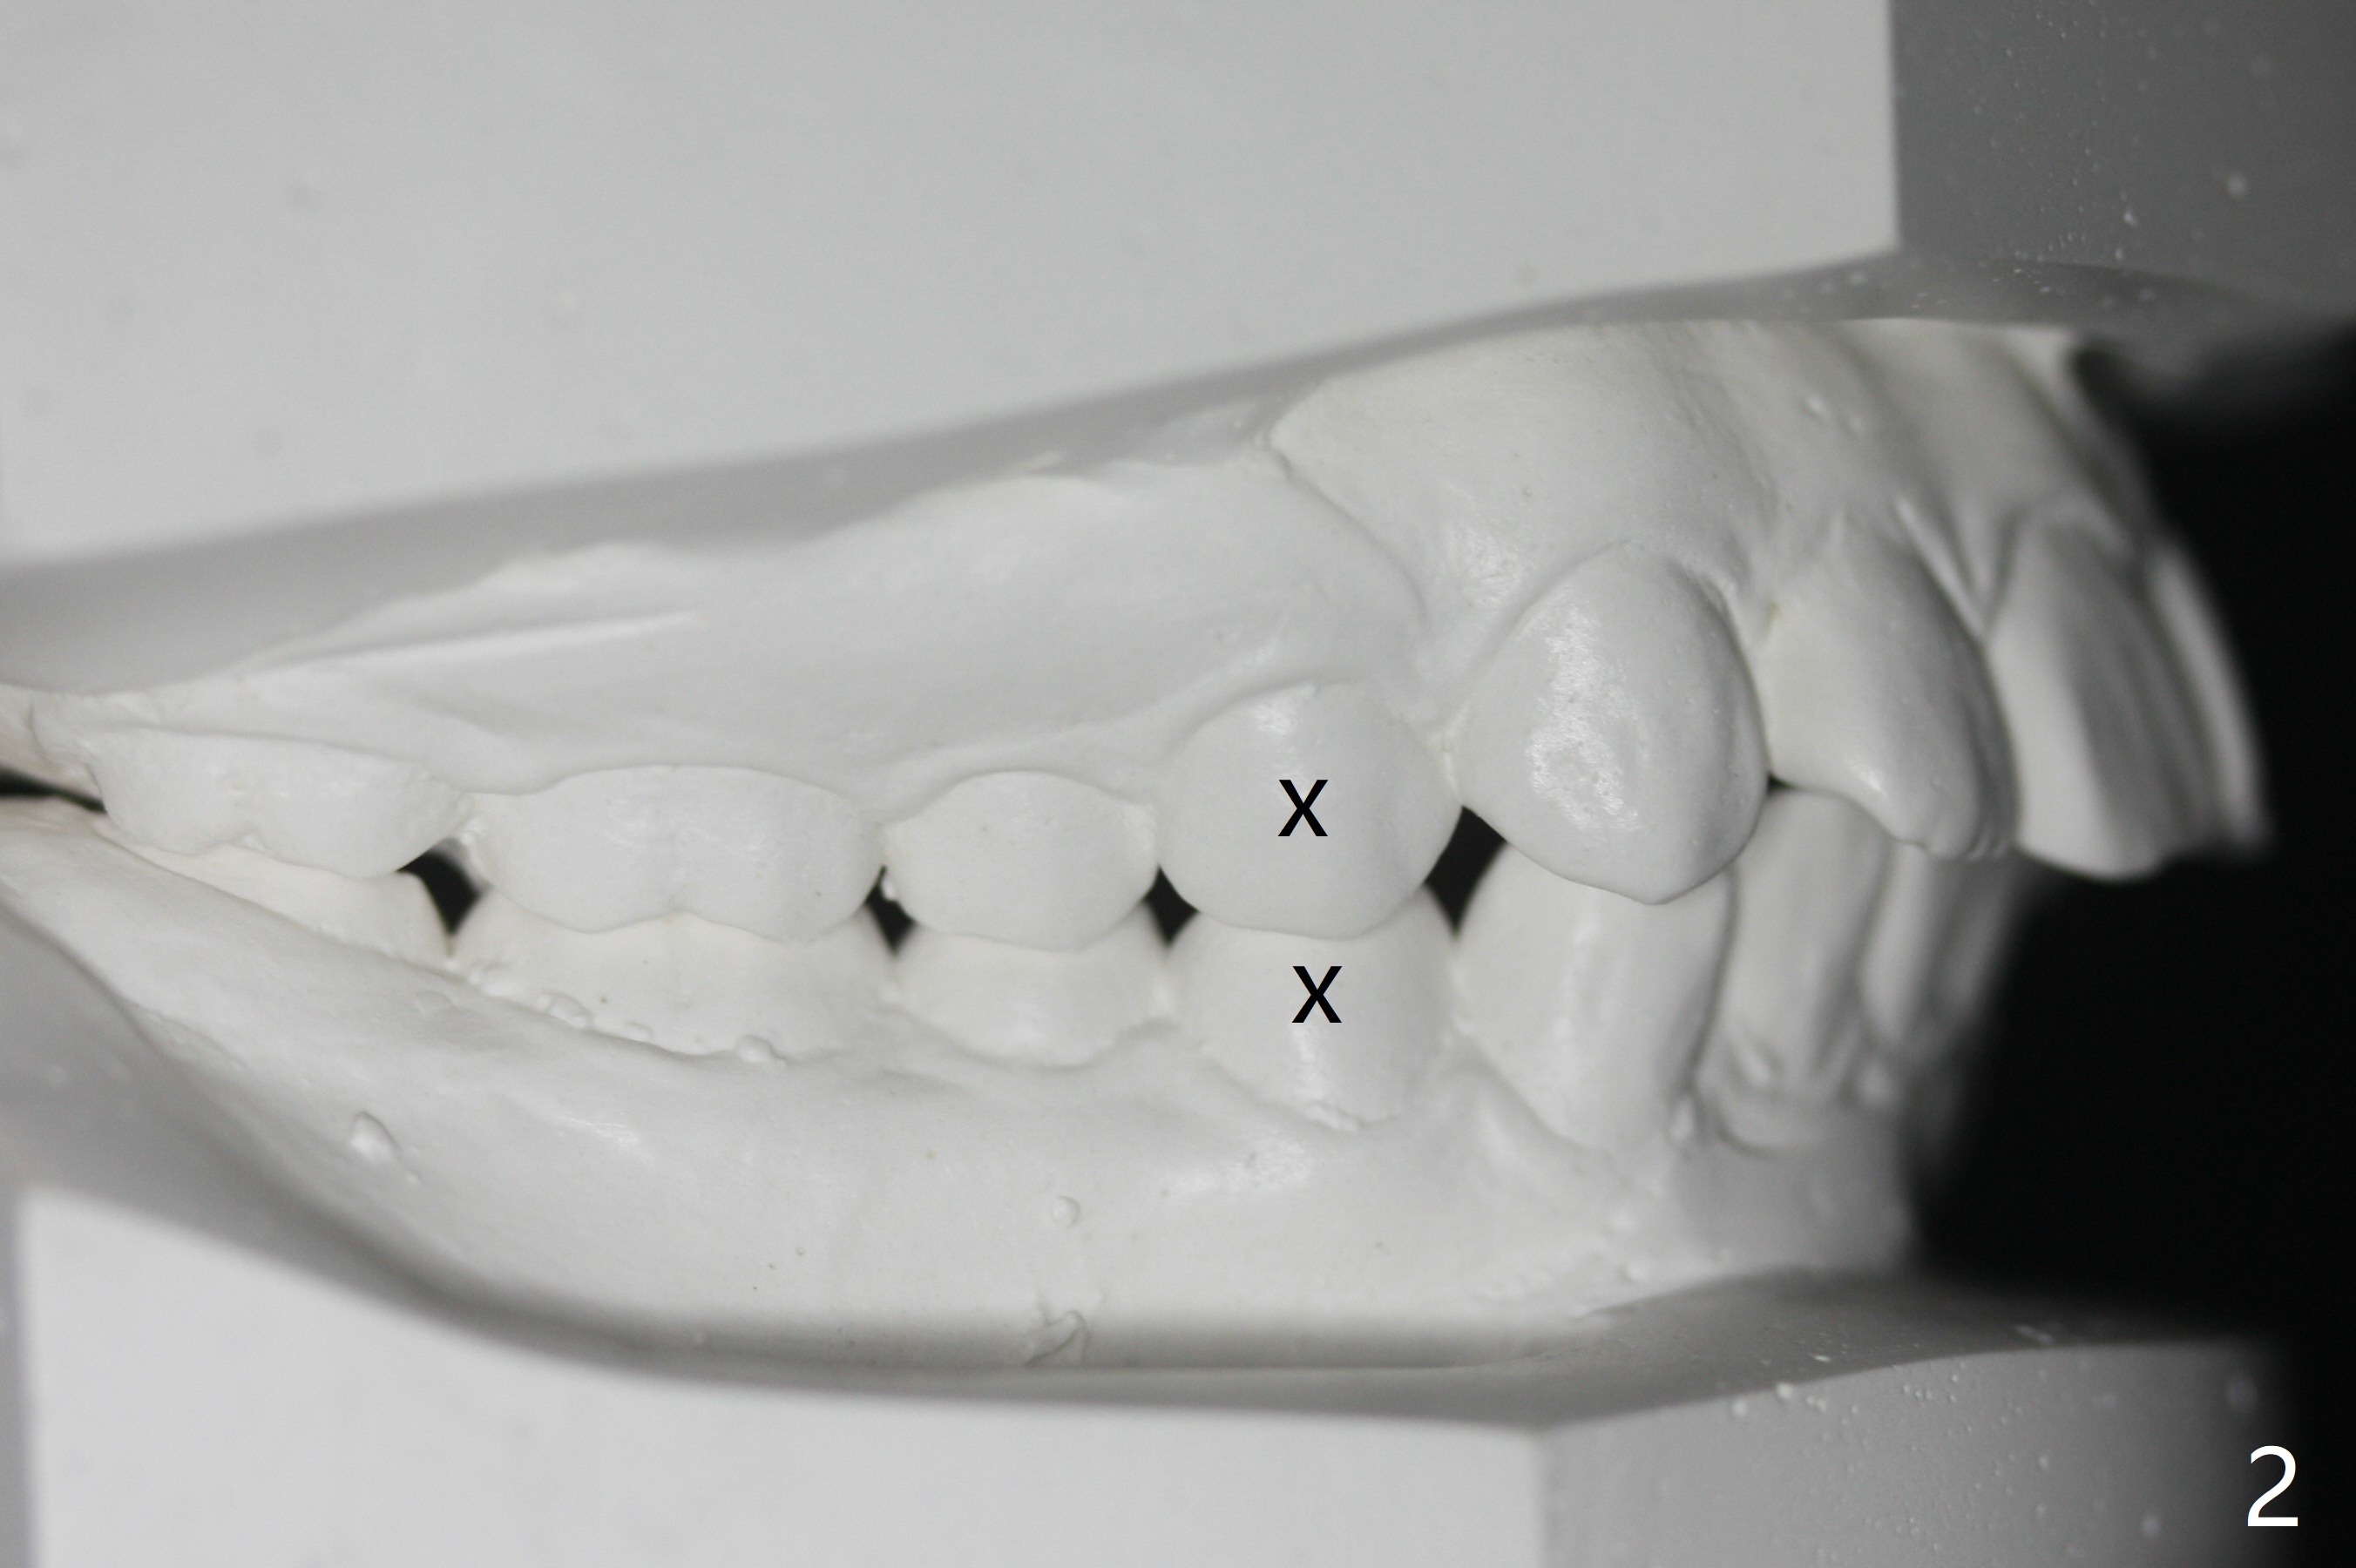

I Malocclusion

The 1st step to correct severe Class II Division I malocclusion (Fig1) is extraction of 4 of the 1st bicuspids (Fig.2 X). Following placement of 16x16 wires, start Class II retraction (Fig.3 red line) as well as distalization of U3 (Fig.4). When canine Class I relation is established (Fig.5 horizontal arrow (using power chain between L3/5)), arch wire sequence should be able to intrude the incisors (vertical arrows). Finally the lower 2nd bicuspid and molars are mesialized (Fig.6 arrow).